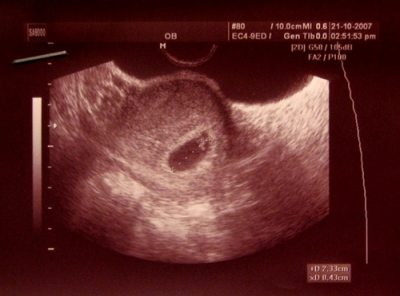

Հիմա արդեն եկել է ժամանակը վերջապես հավատալու, որ հղիությունը սկսված է: 5-րդ շաբաթում հղիության նշաններն ու զգացողությունները բավականին ցայտուն են՝ վաղ տոքսիկոզ (սրտխառնոց` առավոտյան, անգամ` փսխում): Քնկոտությունն ու կրծքագեղձերի բարձրացած զգայունությունը հուշում են, որ սխալմունք այլևս չկա: Բայց եթե դեռ կասկածում եք, պետք է հղության թեստ, արյան հետազոտություն կամ տրանսվագինալ ուլտրաձայնային հետազոտություն կատարել: Այդ դեպքում բժիշկը կհաստատի հղիության փաստը և խորհուրդներ կտա հետագա անելիքների վերաբերյալ:

Սկսում են ձևավորվել պտղի ներքին օրգանները՝ լյարդը, ենթաստամոքսային գեղձը, վերին շնչուղիները (կոկորդ և շնչափող) և սիրտը: Ուլտրաձայնային զգայուն սարքն արդեն այս շրջանում կարող է ցույց տալ ողնուղեղային լարը և, այսպես կոչված, նյարդային խողովակը, որը հետագայում դառնալու է երեխայի ողնաշարը և ողնուղեղը: Նյարդային խողովակի երկարությամբ զարգանում են սոմիտները՝ հյուսվածքների սեգմենտները, որոնցից ավելի ուշ առաջանալու է մկանային հյուսվածքը: Դեղնուցային պարկը սկսում է արտադրել գոնոբլաստներ՝ առաջին սեռական բջիջները, որոնք` տղայի դեպքում, դառնալու են սպերմատոզոիդներ, իսկ աղջկա դեպքում`՝ ձվաբջիջներ: